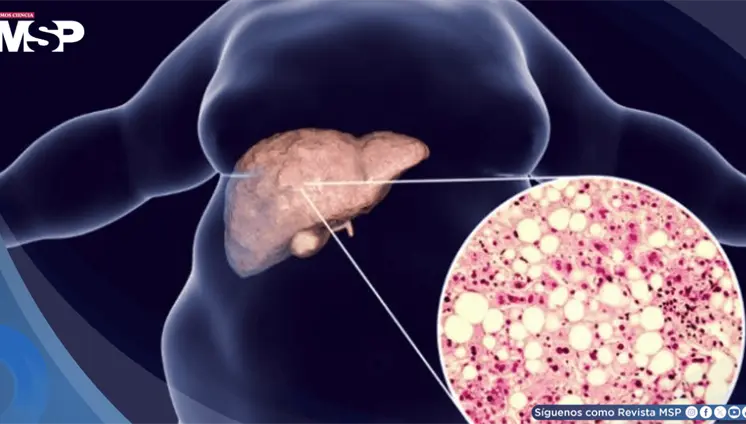

Una condición crónica que afecta a 1 de cada 5 personas con enfermedad...